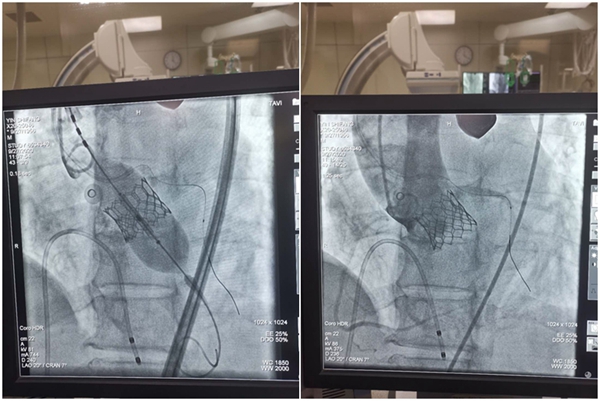

在心臟超聲科和麻醉科的默契配合下,張恒、吳士禮、劉進軍、唐壁、湯陽等醫(yī)生密切協(xié)作,經患者右股動脈入路在左主干保護下將Edwards Sapien3球囊擴張式瓣膜輸送系統(tǒng)順利跨瓣,隨后擴張球囊精準定位后成功釋放瓣膜。瓣膜釋放植入后,即刻檢測跨瓣壓差從術前的110mmHg降低到10mmHg,無殘余瓣周漏,標志著手術成功。

(術前跨瓣壓差110mmHg,術后降低到10mmHg)

(球囊擴張釋放瓣膜,對冠脈開口無影響,無瓣周漏)